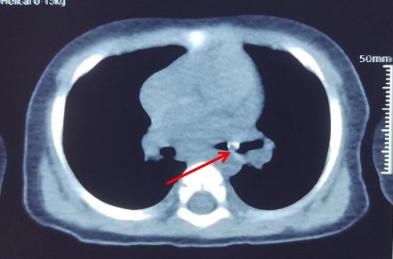

佛山市婦幼保健院在微信公眾號發文講述事件,指小周誤吞黃皮核後,家人初時覺得小周沒有甚麼異常,但後來小周日漸咳嗽、氣喘,多次看醫生都沒有明顯改善,直至去到佛山市婦幼保健院接受詳細檢查,才發現小周「氣管遠端-右主支氣管」有柱狀異物,並有「左肺肺炎」。

醫生分析,異物、即黃皮核落入氣管已有10天,不排除肉芽增生及黏膜炎症,加上黃皮核直徑大,極可能堵塞氣管開口,造成窒息、肺不張,甚至呼吸衰竭等危險,必須盡快做手術取出。

手術期間,醫生更發現,由於氣管環境溫暖、潮濕,黃皮核已經發芽、膨脹,大大增加取出難度。經過一場「拉鋸戰」,這顆發芽黃皮核終於從小周氣管內安全拔出。